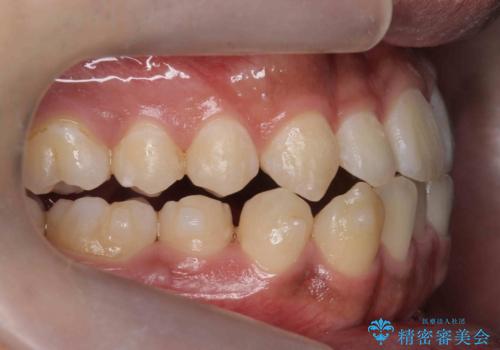

骨格性の受け口 非抜歯で下の歯を後ろに下げる インビザラインで インプラント矯正

- 受け口を主訴に来院。

他院でマウスピース矯正を始めたが、担当医に不信感をもち転院。

治療により受け口が改善し、下あごの輪郭も若干後ろに下がった印象になりました。

当院では下の歯を後ろに下げるため矯正用ミニスクリューを用いてしっかり移動を行う等ご説明をし、治療開始しました。